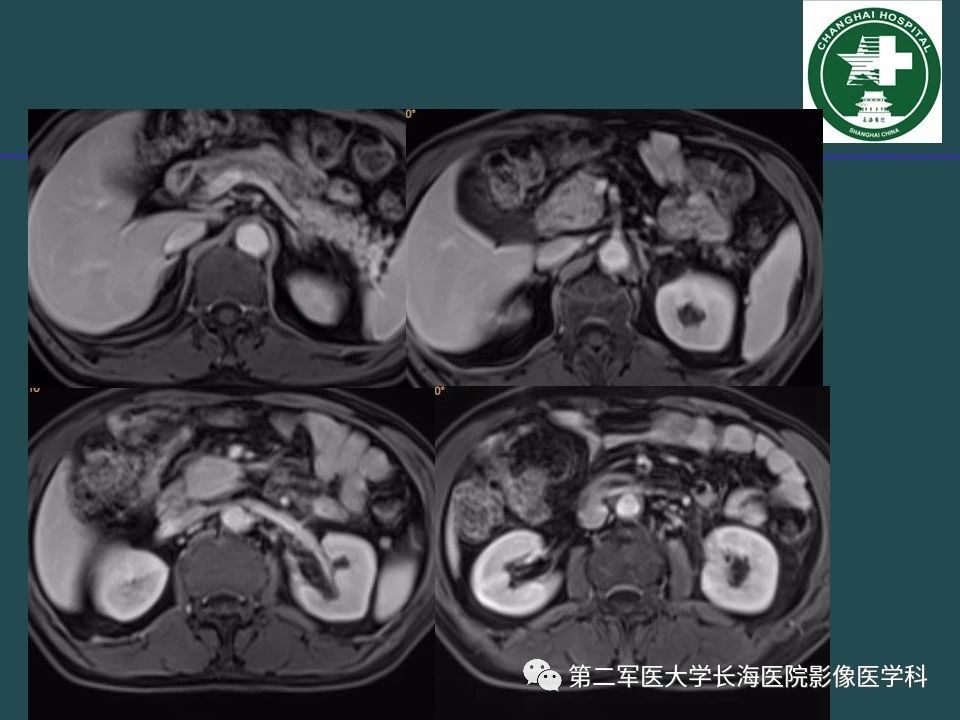

常见的腹膜后占位诊断及鉴别诊断

来源:第二军医大学长海医院影像医学科